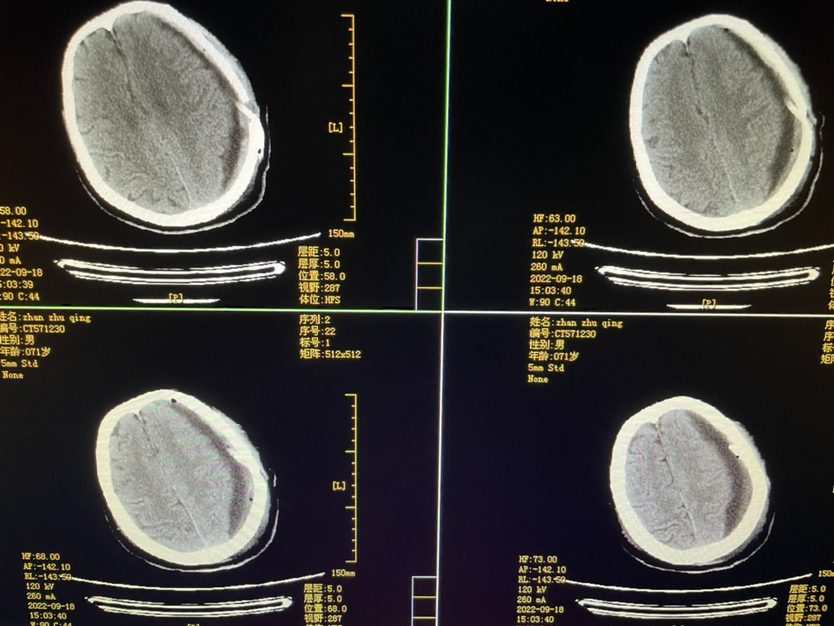

448859,头疼四肢乏力4天,71y